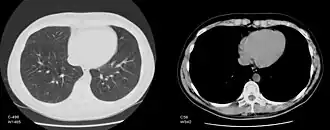

Обычный компьютерный монитор способен отображать до 256 оттенков серого цвета, некоторые специализированные медицинские аппараты способны показывать до 1024 оттенков. В связи со значительной шириной шкалы Хаунсфилда и неспособностью существующих мониторов отразить весь её диапазон в чёрно-белом спектре, используется программный перерасчёт серого градиента в зависимости от выбранного интервала шкалы. Чёрно-белый спектр изображения можно применять как в широком диапазоне («окне») денситометрических показателей (визуализируются структуры всех плотностей, однако невозможно различить структуры, близкие по плотности), так и в более-менее узком с заданным уровнем его центра и ширины («лёгочное окно», «мягкотканное окно» и т. д.; в этом случае теряется информация о структурах, плотность которых выходит за пределы диапазона, однако хорошо различимы структуры, близкие по плотности). Изменение центра окна и его ширины можно сравнить с изменением яркости и контрастности изображения соответственно.

КТ-снимок грудной клетки в лёгочном и мягкотканном окнах (на изображениях указаны параметры центра и ширины окна)